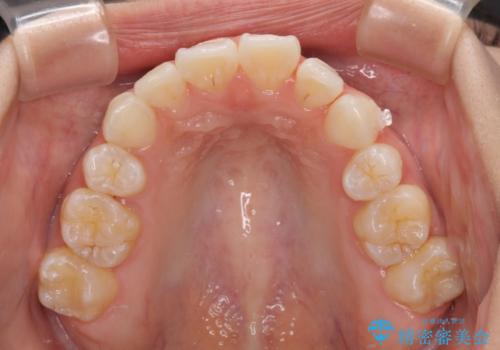

- 上下前歯の叢生を気にして来院された患者様です。

インビザラインでの治療を希望されていて、デコボコの程度が中等度であり、安価なパッケージにて対応可能と判断されたため、インビザライン・モデレートを用いて矯正治療を行うこととしました。

インビザライン・モデレートは、製作できるアライナーの枚数に制限があるため、移動可能な量に限りがあるものの、インビザライン・ライトよりも枚数が多いため、幅広い症例に対応可能です。